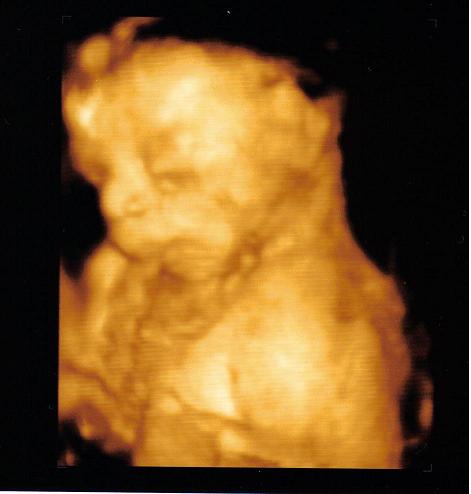

Muffin: A páromnak is megmutattam a képet és azt mondta, hogy szerinte kreált a kép. Ilyet nem lehet lekapni. Nagyon aranyos a babucid!!! Olivér is farfekvéses volt így császárral született. Ezt későn tudtam meg és már nem lehetett mit tenni.

tita, köszi a jótanácsokat :) párodnak meg mondd meg hogy kreált a kép, mi kreáltuk ami rajta van :) :)

Wera: NAGYON NAGY GRATULA NEKTEK, NAGYON SZÉPEK VAGYTOK!!!!! GYÖNYÖRŰEK A KÉPEK. Mi is csináltattunk olyan képet ahol látszik, hgogy Olivér a pocakomban van. Azt neki csináltattuk. Ha nem baj megmutatom. Bocsi, hogy én is mutogatom a képeimet. Most neked van erre jogosultságod!!! :oops: